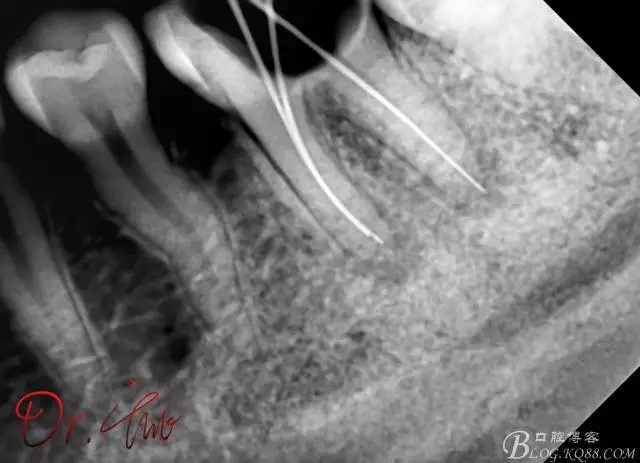

拍片確定長度

640.webp (1).jpg